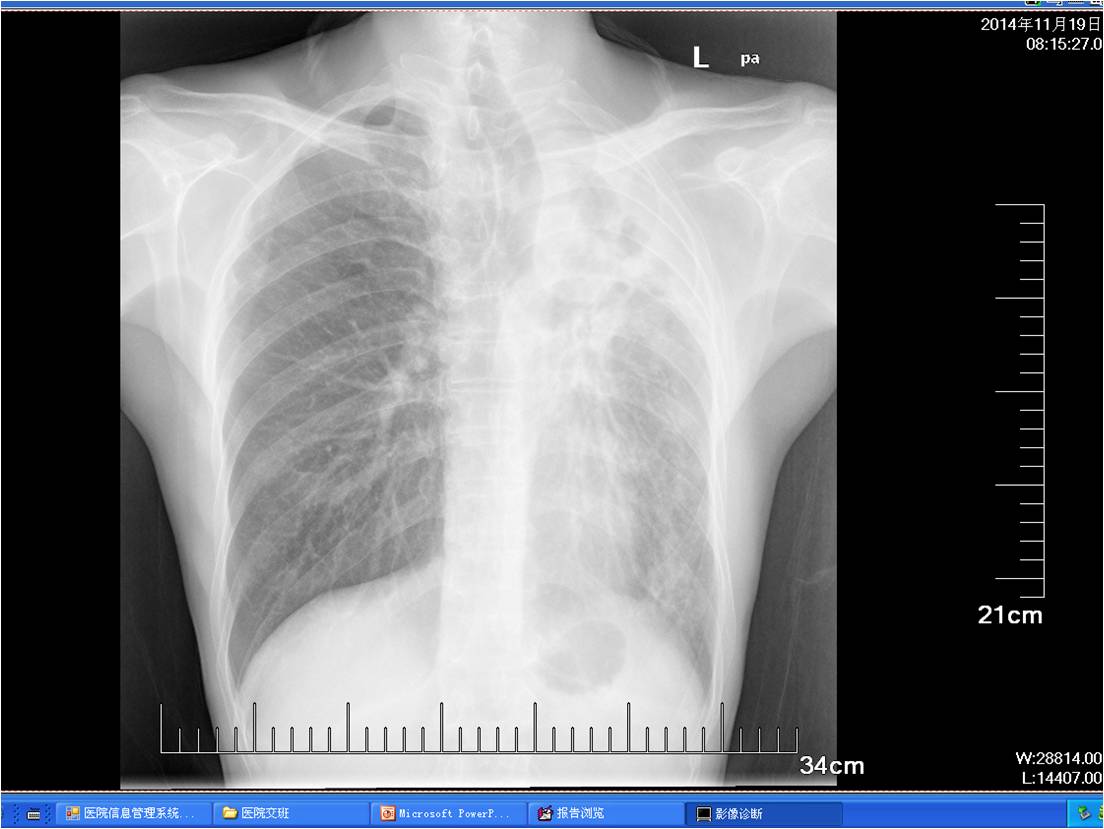

术前胸片

术前胸片